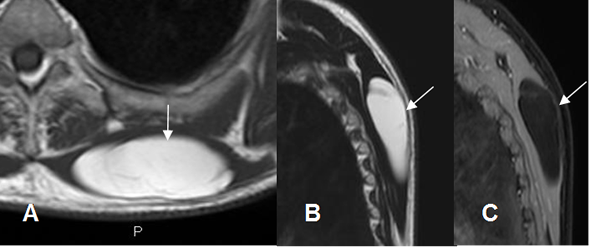

Fig 163 B. Lipoma arborescente.

A: Rx AP. No se encuentran alteraciones.

B: RM sagital en STIR. Abundante derrame articular, con proliferación sinovial hipointensa.

C: RM axial en T1 y D: RM coronal en T1 con contraste. La proliferación sinovial sigue la señal de la grasa subcutánea y realza con el contraste, por lipoma arborescente.